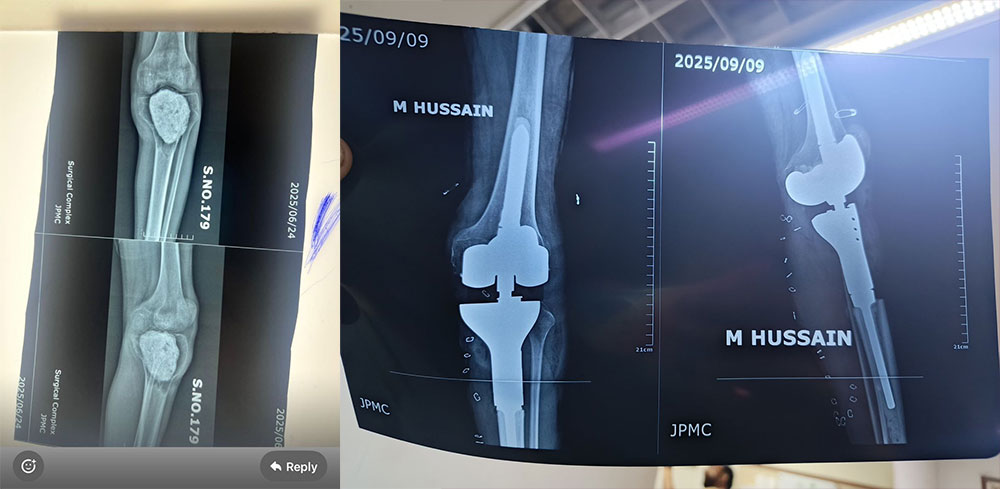

KARACHI: In a landmark achievement, surgeons at Jinnah Postgraduate Medical Centre (JPMC) successfully operated on a 26-year-old male patient suffering from a recurrent Giant Cell Tumor (GCT) in the proximal tibia. This marks the first-ever surgery of its kind in the history of JPMC, where the limb was salvaged and joint mobility restored through advanced surgical techniques.

The complex procedure involved a wide margin excision, followed by reconstruction using a megaprosthesis and flap, ensuring both cancer clearance and limb preservation.